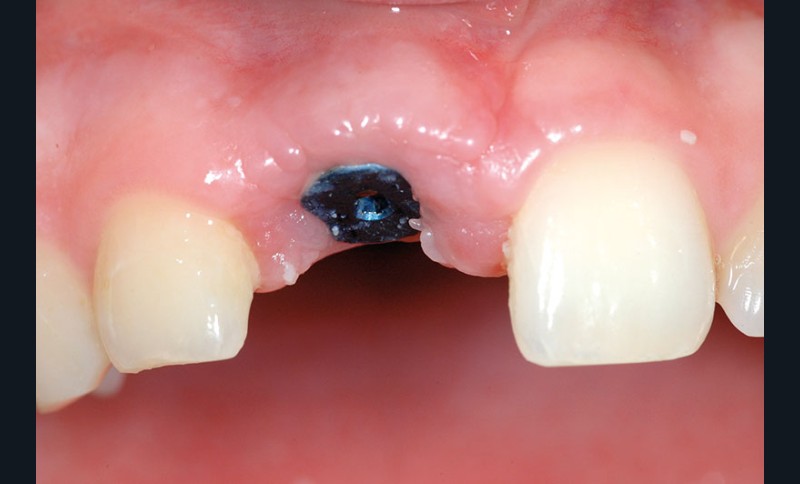

L’implant a été posé alors que la patiente était âgée de 17 ans (le 13 août 2004), à la suite d’un traumatisme entraînant la perte de cette dent (fig. 2a à d), puis la couronne a été posée 5 mois plus tard (le 7 janvier 2005).